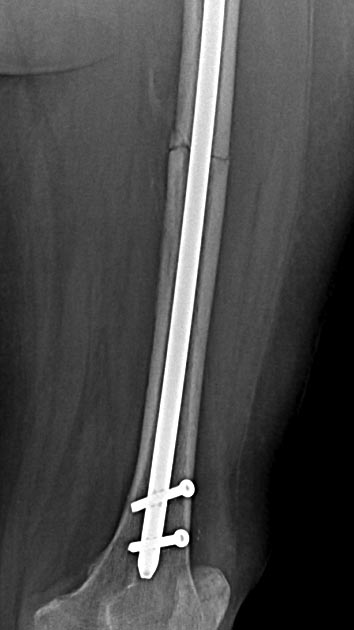

Две несросшихся шейки бедра, пацинтка 27 лет, травме 5 месяцев

Травма 5 месяцев назад кататрвма.

БИОС плеча, Чкдо на л/запястный сустав, Биос левого бедра, Мос правой шейки

бедра винтами.

Причина обращения -выявленный ложный сустав шейки левого бедра. При

дообследовании выявлен несросшийся перелом шейки бедра на винтах.

Опороспособность обеих н/конечностей резко снижена, может стоять на правой,

передвигается на каляске.Что думаем: слева однозначно протез, но бедро не

срослось, менять гвоздь на пластину, пластина или которкая, или опасность

конфликта с ножкой протеза, можно подождать консолидации и разбираться с